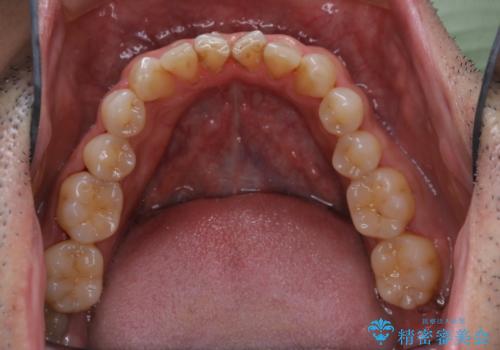

開始前

治療途中